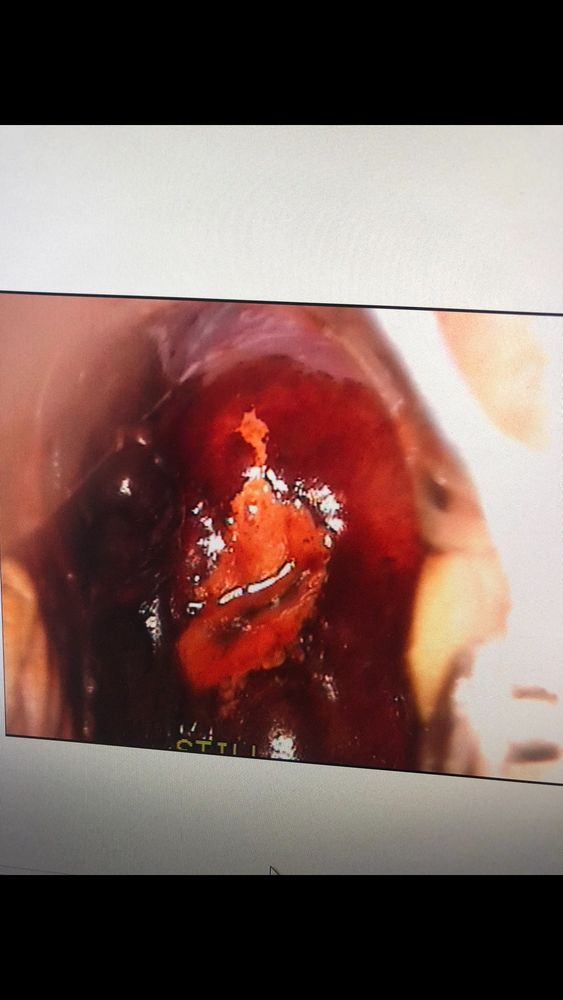

Фото кольпоскопии с сомнительным участком (при окрашивании йодом)